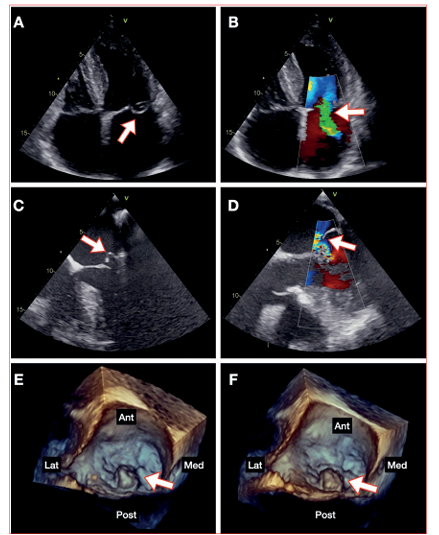

De la paraclínica solicitada destaca un NT-proBNP de 2600 pg/mL y un ecocardiograma transtorácico que evidencia insuficiencia mitral severa primaria por prolapso del velo posterior de la válvula mitral, bioprótesis aórtica normofuncionante y FEVI conservada. El ecocardiograma transesofágico evidencia una válvula mitral mixomatosa, con prolapso del festón P2, que determina un jet de insuficiencia excéntrica severo, sin rotura de cuerdas tendinosas ni otras alteraciones de aparato valvular (figura 1, video 1).

Figura 1 Ecocardiograma basal. A: Transtorácico ventana apical 4 cámaras, se observa prolapso de valva posterior (flecha). B: Doppler color con jet de insuficiencia mitral severa (flecha). C: Transesofágico 0 grados, se observa prolapso de festón P2 (flecha). D: Doppler color con jet de insuficiencia severa (flecha). E y F: Transesofágico 3D (“vista de cirujano”), se observa prolapso de festón P2 (flecha). Ant: anterior. Post: posterior. Med: medial. Lat: lateral.